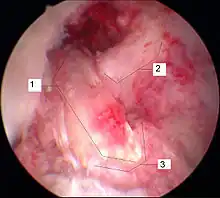

Arthroscopie

L'opération proprement dite commence par l'introduction de l'arthroscope dans le genou du patient. Ceci permet de confirmer définitivement le diagnostic de rupture de LC. Les autres blessures, en particulier celles des ménisques, peuvent être soignées avant la reconstruction du LC.

Prélèvement du transplant

Le premier temps de l'opération est le prélèvement du transplant. Une incision d'environ 4 cm dans la peau sur la partie interne de la tête du tibia, au-dessus de la «patte d'oie» permet le prélèvement successif sur les tendons semi-tendineux et gracile. Les prélèvement sont faits sur les deux tendons avec un « couteau à tendon », et ont une longueur d'environ 28 cm. Ils sont pré-tendus avec un dispositif spécial, et cousus ensemble en un cordon multiple, par exemple quadruple. La longueur du transplant est alors de 7 cm, avec un diamètre d'environ 7 mm. Le transplant est alors cousu au moyen d'un fil spécial dans les deux trous internes d'un disque ovale à quatre trous (endobouton). Ce fil spécial n'est pas résorbable.

Élimination des restes de ligament croisé et percement des canaux osseux

Les restes du LCA rompu sont éliminés sous arthroscopie. Pour cela, on utilise un outil motorisé de découpe et d'aspiration. À l'aide d'un appareil à positionner, la position pour le percement d'un canal à travers la tête du tibia est déterminée, et le trou est fait. La même procédure est appliquée au percement à travers le fémur. Ce canal se rétrécit vers le haut et a une longueur d'environ 35 mm. La partie plus large de ce canal est destinée à recueillir le transplant, la partie étroite à faire passer l'accrochage du transplant.

Enfilage du transplant

Le transplant est inséré au moyen de deux fils de traction du bas vers le haut dans les trous percés. Au moyen d'une vis creuse, le transplant est fixé au fémur. L'extrémité sortant du canal du tibia est pré-tendue et fixée par coincement avec une vis d'interférence (vis delta). Puis les orifices opératoires sont recousus, en laissant un drain aspiratif. La durée de l'opération est environ de 45 à 90 min.